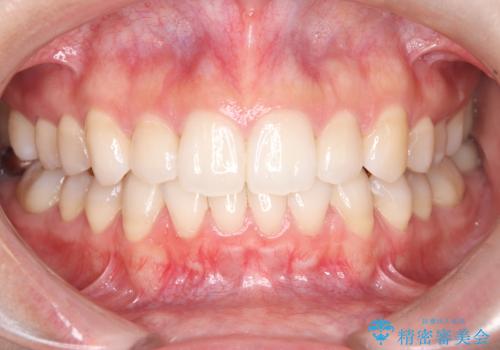

前歯のデコボコと開口を改善し、美しい口元へ

担当医 河口智英